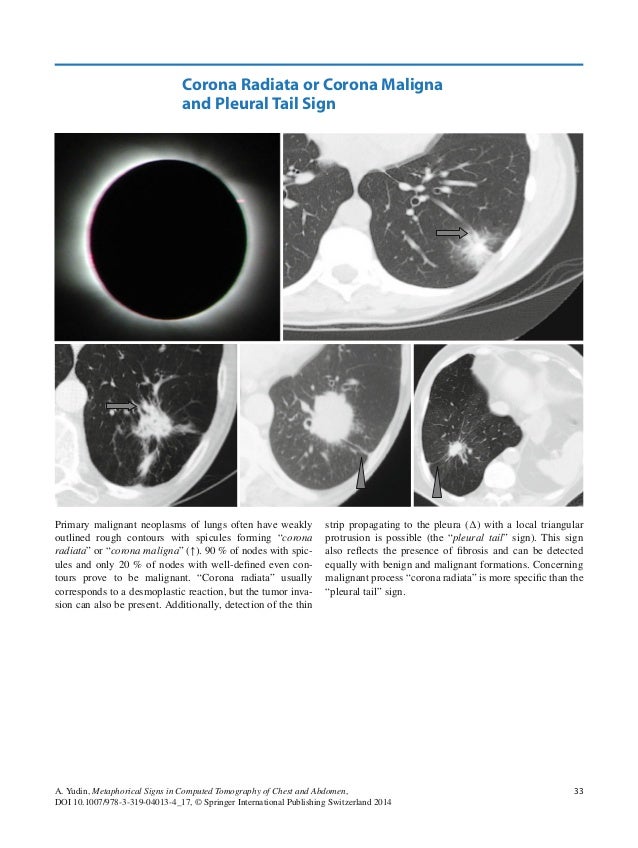

Corona Radiata Or Corona Maligna And Pleural Tail Sign Springerlink

link.springer.com